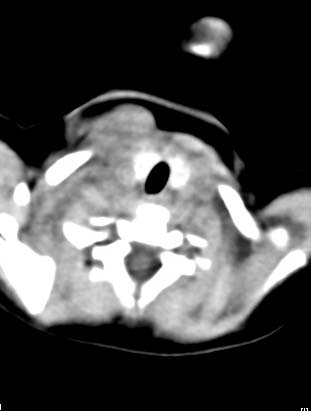

以下是引用zjzjr在2008-12-18 11:20:00的发言:[br]右颈部软组织肿块,性质待定(神经源性肿瘤等排),上下径较长,不太支持肿大淋巴结.